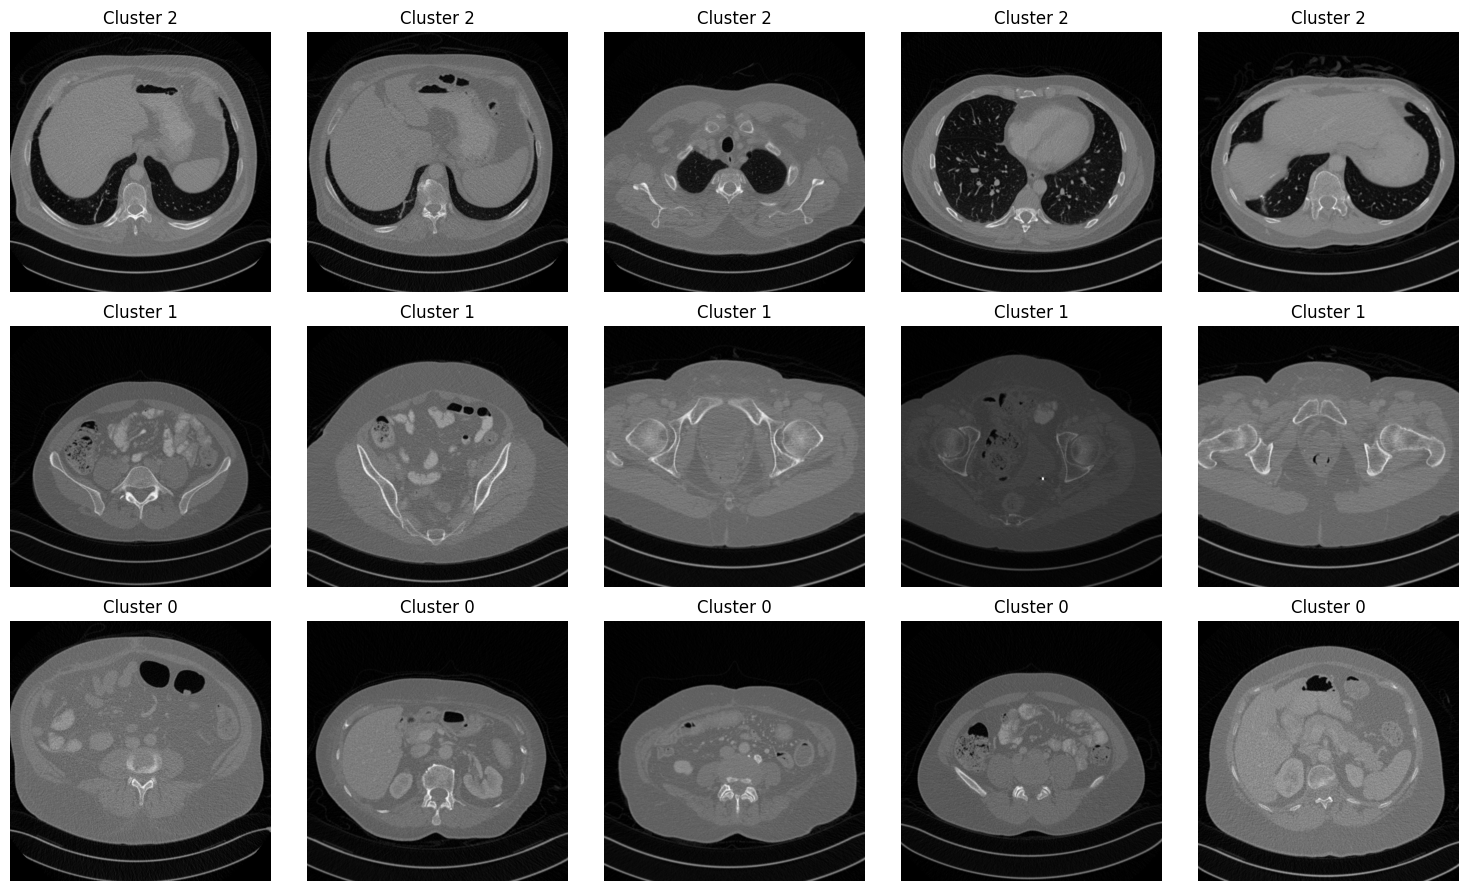

These high-dimensional semantic similarity vectors are reduced to 2D representations using Principal Component Analysis (PCA). We then apply K-means clustering (k=3) to group these vectors based on their anatomical representations. To characterize each cluster, we randomly sample hundred images per cluster, process them with BiomedCLIP to estimate the probability of each structure, and compute the mean probability for each structure within every cluster. Figure 4 illustrates representative examples from each cluster and the PCA results are provided in Appendix C.

[Uncaptioned image]

Figure 4: Five randomly selected images per cluster. Cluster 2 focuses on lungs, cluster 1 on pelvis, and cluster 0 on abdomial organs.

• Cluster 0 (1,938 images) is associated with abdominal organs such as spleen, pancreas, and abdomen.

• Cluster 1 (2,561 images) consists mostly of pelvis.

• Cluster 2 (1,437 images) includes mainly lungs.